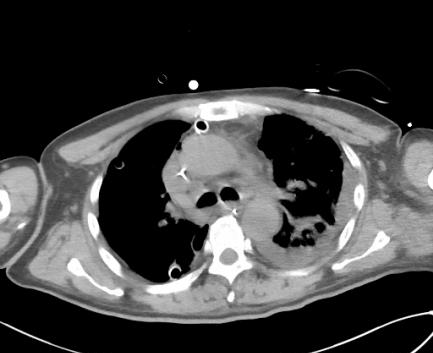

经过十七天的治疗,医护人员与死神来回拉锯,患者的颌面部、颈部红肿、疼痛以及肺部感染等症状明显缓解,体温恢复正常,逐渐脱离呼吸机。目前,患者已转入普通病房,拔除全身引流管,可下床活动,全身状况好转。

▲治疗第5天颈部(冠状位),胸部(轴位)